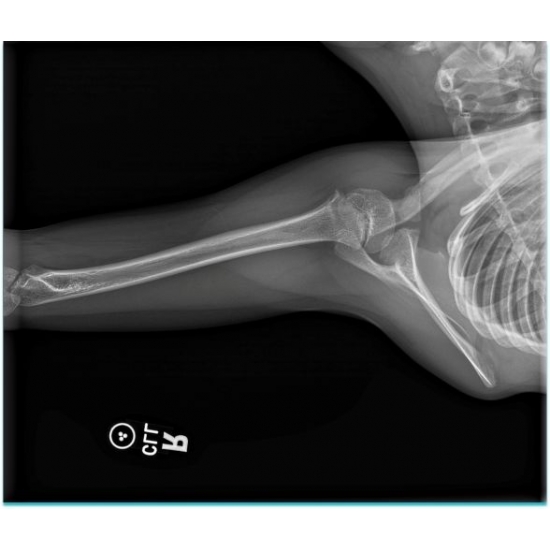

| Monkey Bar Mishap: A Unique Scapulothoracic Injury And Presentation - Page #3 | |||